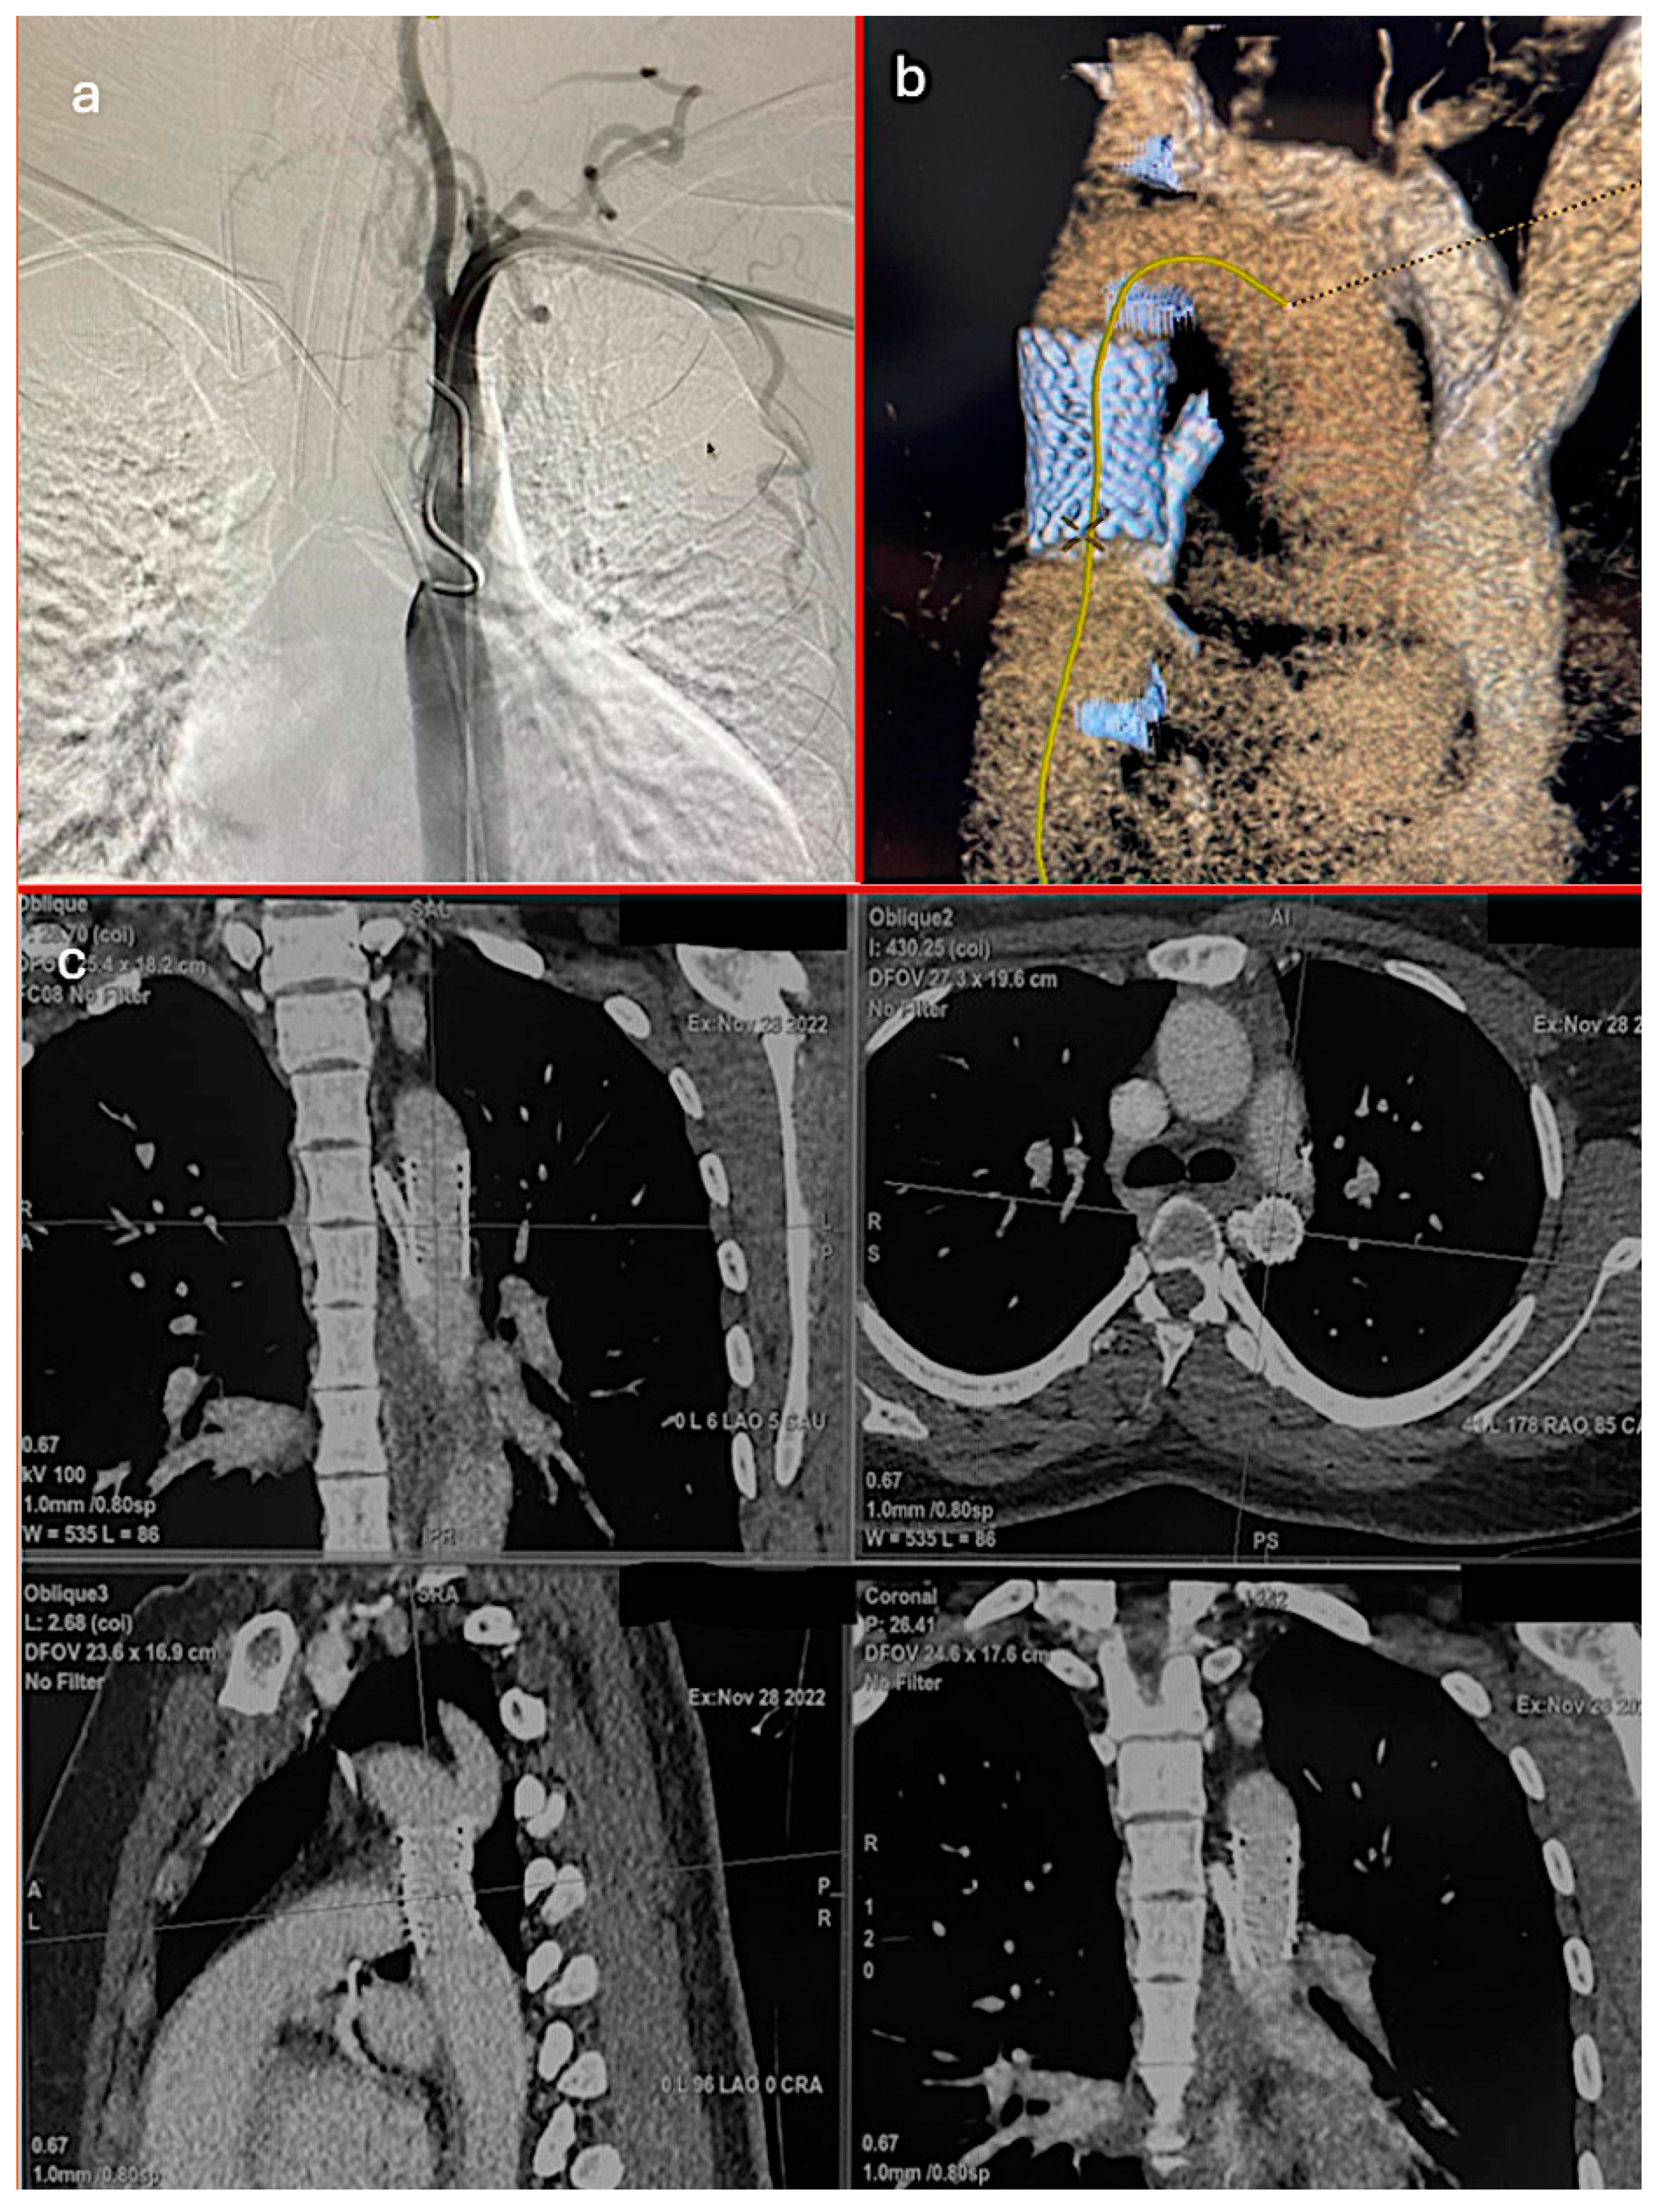

Regarding the timing of the interventions, 67 patients (97.1%) underwent elective repairs, and 2 (2.9%) required emergent procedures. The repair techniques included endovascular treatment in 17 patients (24.6%), surgical end-to-end anastomosis in 33 patients (47.8%), and surgical patchplasty in 19 patients (27.5%). Figure 1 provides a detailed visualization of the aortic coarctation case in one of our patients. The postoperative CT scan confirmed the proper positioning of the aortic graft and chimney ARSA stent, illustrating the favorable outcome of the surgical intervention (Table 1, Graph 1, Figure 2).

Figure 2. (a) Preoperative angiography of coarctation, (b) postoperative 3D CT imaging of aortic graft and chimney ARSA stent, (c) postoperative CT imaging of aortic graft and chimney ARSA stent.